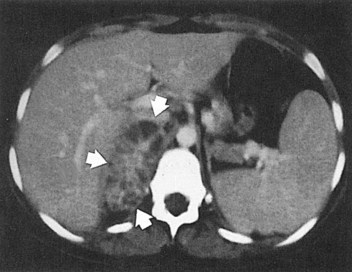

Ultrasonography usually demonstrates strong focal echoes suggesting the presence of intraparenchymal gas (Brenbridge et al, 1979; Conrad et al, 1979). CT is the imaging procedure of choice in defining the extent of the emphysematous process and guiding management (Figs. 10-23 and 10-24). An absence of fluid in CT images or the presence of streaky or mottled gas with or without bubbly and loculated gas appears to be associated with rapid destruction of renal parenchyma and a 50% to 60% mortality rate (Wan et al, 1996; Best et al, 1999). The presence of renal or perirenal fluid, the presence of bubbly or loculated gas or gas in the collecting system, and the absence of streaky or mottled gas patterns is associated with a less than 20% mortality rate. Obstruction is demonstrated in approximately 25% of the cases. A nuclear renal scan should be performed to assess the degree of renal function impairment in the involved kidney and the status of the contralateral kidney.

The opportunity for pathologic confirmation of acute bacterial nephritis is rare. The kidney may be edematous. Focal acute suppurative bacterial nephritis caused by hematogenous dissemination of bacteria to the renal cortex is characterized by multiple focal areas of suppuration on the surface of the kidney (Fig. 10–15). Histologic examination of the renal cortex shows focal suppurative destruction of glomeruli and tubules. Adjacent cortical structures and the medulla are not involved in the inflammatory reaction. Acute ascending pyelonephritis is characterized by linear bands of inflammation extending from the medulla to the renal capsule (Fig. 10–16). Histologic examination usually reveals a focal wedge-shaped area of acute interstitial inflammation with the apex of the wedge in the renal medulla. Polymorphonuclear leukocytes or a predominantly lymphocytic and plasma cell response are seen. Bacteria also may be present.

Figure 10–15 Acute focal suppurative bacterial nephritis. A, Surface of kidney. Arrows indicate focal areas of suppuration. B, Renal cortex showing focal suppuration destruction of glomeruli and tubules.

(From Schaeffer AJ. Urinary tract infections. In: Gillenwater JY, et al, editors. Adult and pediatric urology. Philadelphia: Lippincott Williams & Wilkins; 2002. p. 211–72.)